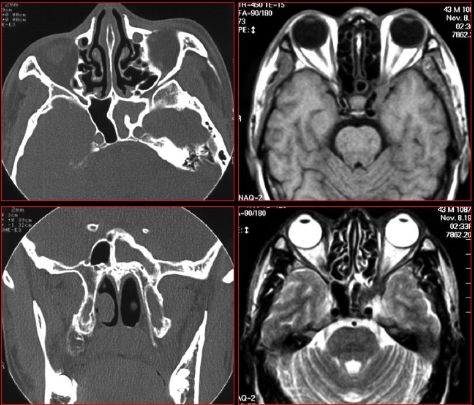

慢性多发鼻窦炎—MRI

MRI表现:

★ 侵袭为黏膜炎性水肿和蜂窝织炎,T1WI为低信号,T2WI为高信号

★ 慢性为明显低信号,钙化,霉菌内含有铁和锰等顺磁性物质,含蛋白质高的黏液等。

★ 反应性肉芽肿或鼻窦炎T1WI为低信号、T2WI为高信号

★ 增强扫描病变周边黏膜明显强化

★ 显示侵犯眼眶、颅底、颅内实质或硬脑膜窦